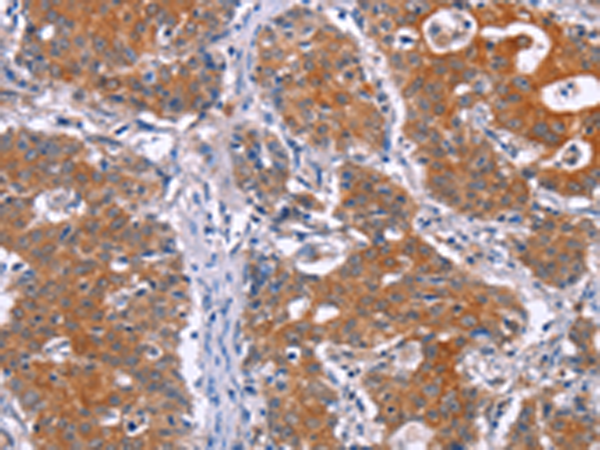

分类: 科研抗体货号: P04116别名: CODA; MMP18; RASI-1应用: WB,IHC反应种属: Human